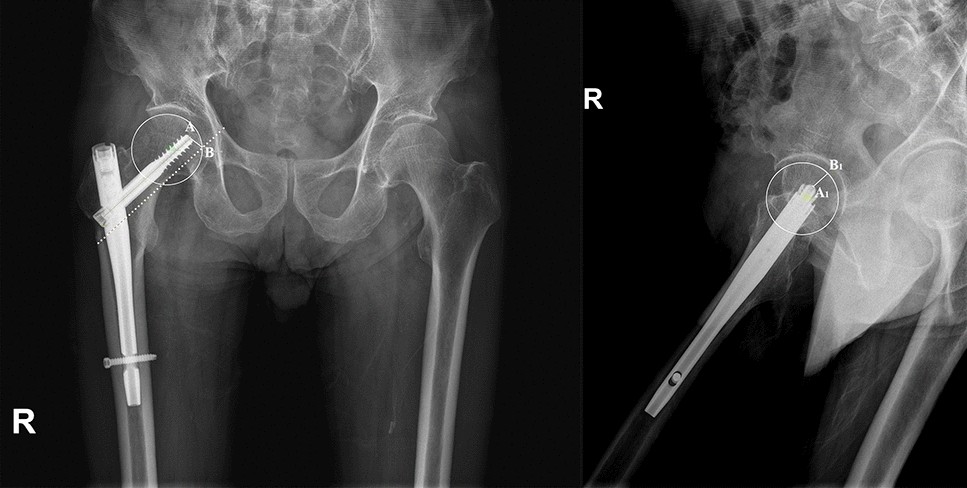

Figure 5

Assessment of the CalTAD in the anterior–posterior plane and the lateral plane. The Calcar Tip Apex Distance (CalTAD) is represented by the sum of AB and A1B1 distance.